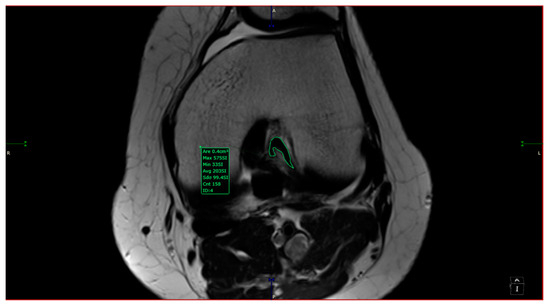

- aICN area: area of the circle defined by three cortical walls of the antero-superior notch (in the custom axial plane/CAP; Figure 3).

- ACL area: area of the closed polygon defined by pointed dots around the cross-section of the anterior cruciate ligament (in the CAP; Figure 4).

- aICN area and ACL area (both appear in Figure 6).